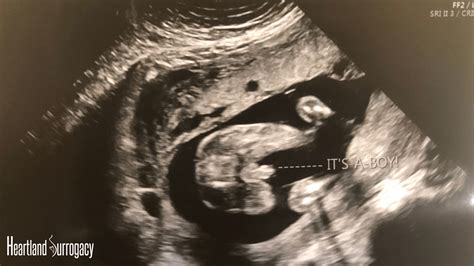

Anatomy Scan 20 Weeks

Reaching the halfway point of your pregnancy is a momentous milestone that brings both excitement and a touch of nervous anticipation. For many expectant parents, the Anatomy Scan 20 Weeks appointment is the most highly anticipated event on the prenatal calendar. This comprehensive ultrasound examination is far more than just a chance to see your baby’s profile; it is a vital clinical assessment designed to evaluate your baby’s development from head to toe. During this window, typically occurring between 18 and 22 weeks of gestation, your healthcare provider gains a clear, detailed picture of how your baby is growing and functioning, providing peace of mind and essential medical information.

The Anatomy Scan 20 Weeks is a mid-pregnancy ultrasound, also known as a level II or anomaly scan. Unlike the early dating scans which primarily confirm pregnancy and estimate the due date, this appointment focuses on the structural development of the fetus. The sonographer will systematically review various organs and physical characteristics to ensure that everything is progressing as expected. It is a highly specialized procedure that requires both a skilled technician and high-resolution imaging equipment to capture the internal structures of your growing baby.

The Anatomy Scan 20 Weeks is often the moment when pregnancy begins to feel truly “real.” Seeing your baby move, hearing their heartbeat, and watching them on the screen can foster a deep sense of connection. While the primary goal is medical assessment, it is also a time for bonding. Do not be afraid to ask questions; your sonographer is there to help you understand what you are seeing. While they may not be able to provide a full medical report on the spot, they can point out features like the baby’s profile or their active movements.